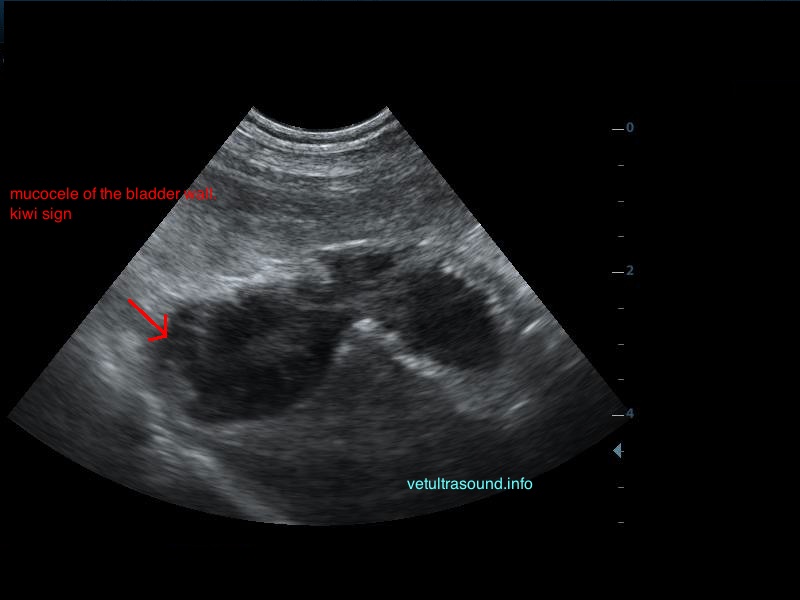

Ήπια ηπατομεγαλία με αύξηση της ηχογένειας του οργάνου, χωρίς παρουσία εστιακών αλλοιώσεων(pic.4). Πάχυνση του τοιχώματος της χοληδόχου κύστης με εικόνα βλεννοκήλης ( kiwi sign) και έντονη υπερηχογένεια στη περιοχή περί αυτού(pic.1&2). Ήπια διάταση της νεφρικής πυέλου, πιθανόν λόγω της πολυουρίας και πολυδιψίας(pic.3). Επασβέστωση στον οπίσθιο πόλο του δεξιού επινεφριδίου και αύξηση των διαστάσεών του(pic.6). Απουσία ασκιτικής συλλογής και παθολογικά διογκωμένων λεμφαδένων.

Η διάγνωση μετά τον υπέρηχο τέθηκε ως βλεννοκήλη της χοληδόχου κύστης με εικόνα χολοκυστίτιδας σε υπόβαθρο πιθανού υπερφλοιοεπινεφριδισμού. Θα πρέπει να γίνει επιβεβαίωση με αιματολογικές εξετάσεις του υπερφλοιοεπινεφριδισμού, καθώς η βλεννοκήλη της χοληδόχου κύστης είναι μία από τις επιπλοκές αυτού.